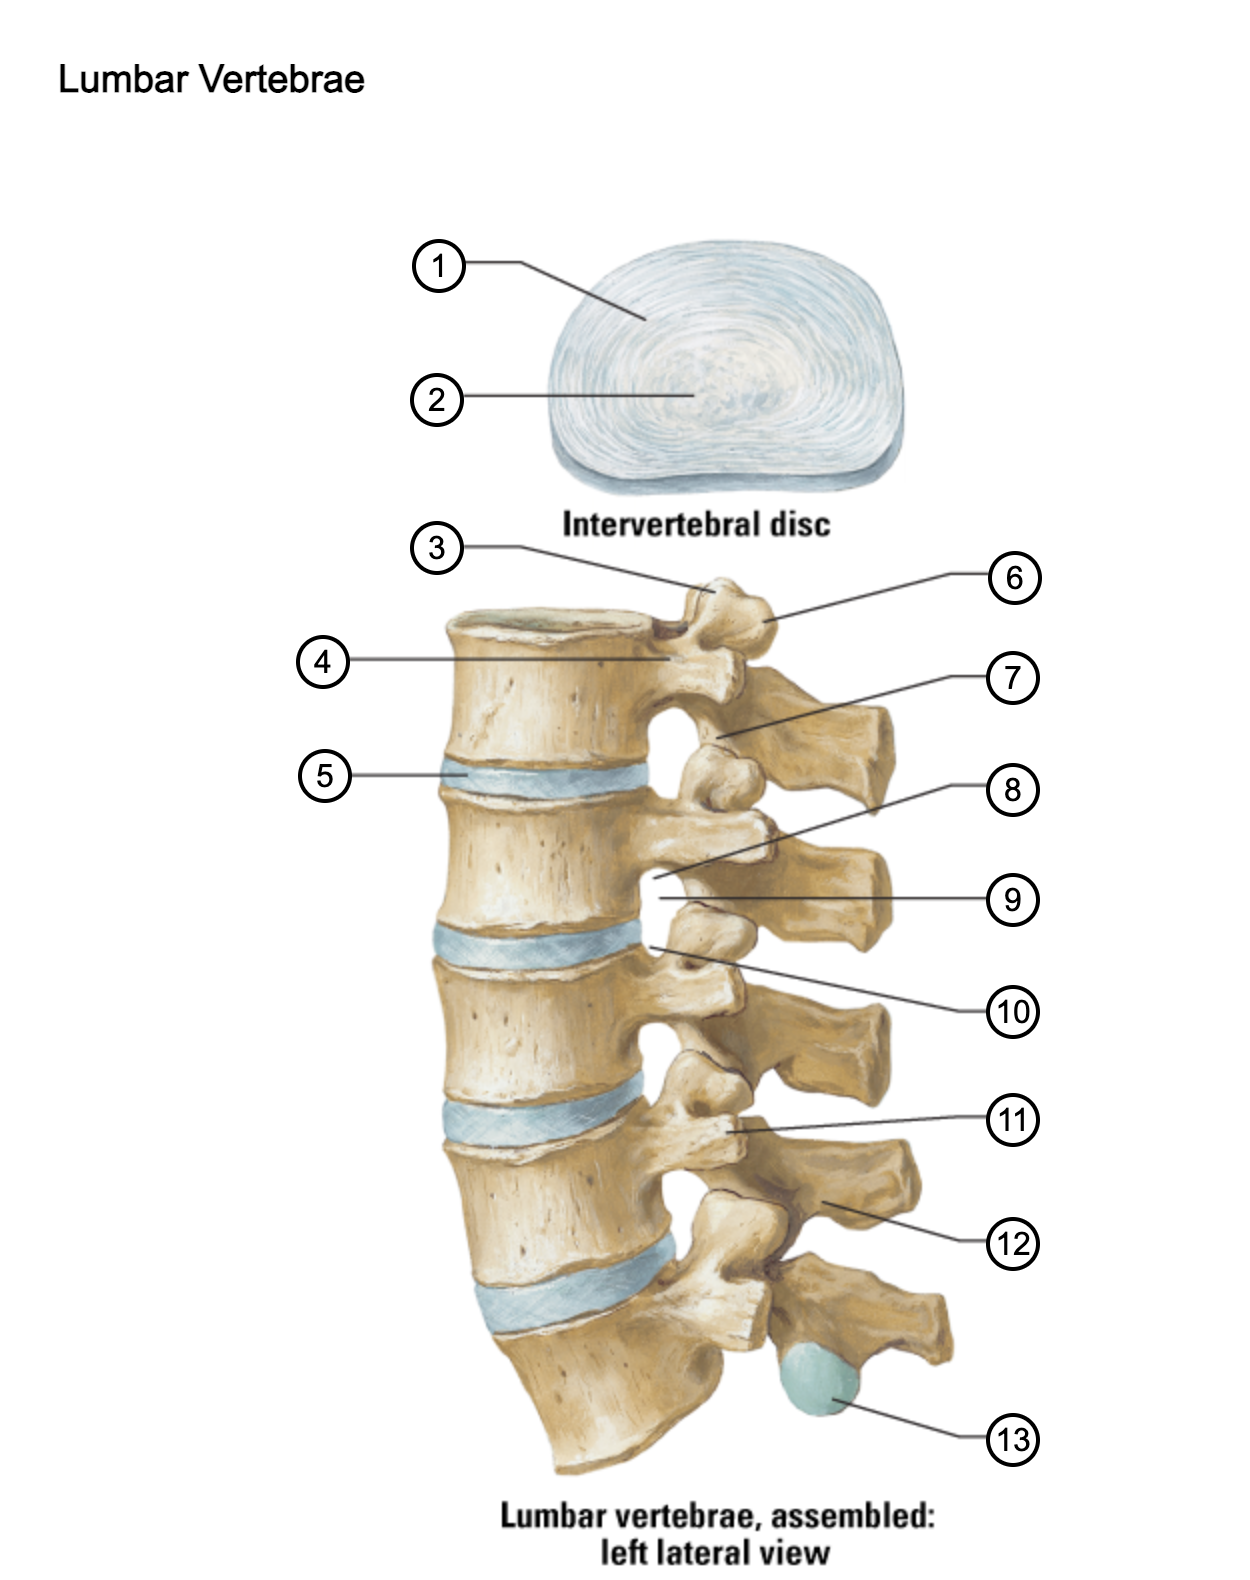

1

anulus fibrosus

2

nucleus pulposus

3

superior articular process

4

pedicle

5

intervertebral disc

6

mammillary process

7

inferior articular process

8

inferior vertebral notch

9

intervertebral notch

10

superior vertebral notch

11

transverse process

12

lamina

13

inferior articular facet